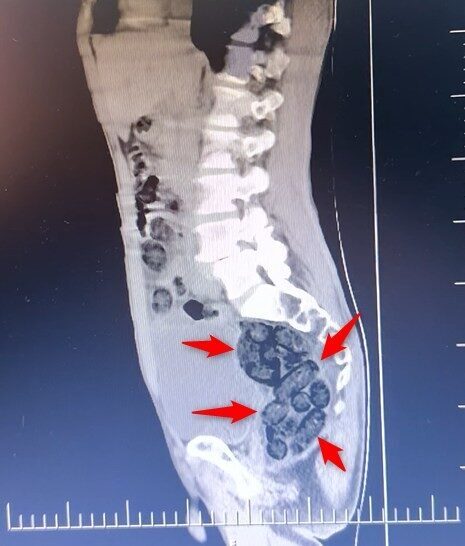

Şüphe üzerine, yabancı uyruklu bir yolcu üzerinde arama yapıldı. Yapılan incelemeler sonucunda, yabancı uyruklu şahsın midesinde 64 parça halinde toplam 472 gram uyuşturucu maddesi metamfetamin bulunduğu belirlendi.

Gözaltına alınan şahsın midesindeki uyuşturucu madde çıkarıldı. Emniyetteki işlemlerinin ardından adliyeye sevk edilen şahıs, çıkarıldığı mahkemece tutuklanarak cezaevine gönderildi.